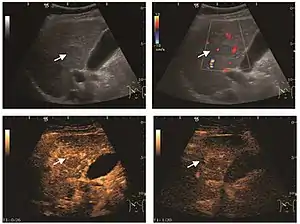

Liver abscess (2D and CEUS). 2D Examination reveals the fluid nature of the mass and imprecise delineation. CEUS examination shows congestion in the surrounding liver parenchyma and excludes a vascular tumor.

Liver abscess have heteromorphic ultrasound appearance, the most typical being that of a mass with irregular shapes, fringed, with fluid or semifluid content, with or without air inside. Doppler examination shows the lack of vessels within the lesion. CEUS exploration shows hyperenhancement during arterial phase close to the lesion, this being suggestive of a liver parenchymal hyperemia. During venous and sinusoidal phase the pattern is hypoechoic, and the central fluid is contrast enhanced. CEUS examination is useful because it confirms the clinical suspicion of abscess. In addition, it allows for an accurate measurement of the collection size and an indication regarding its topography inside the liver (lobe, segment).